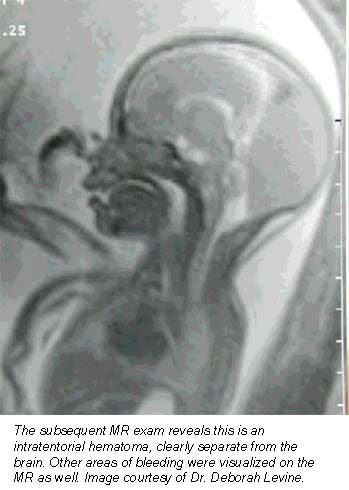

Still more applications are being pioneered at Boston’s Beth Israel Deaconess Medical Center, where researchers are nearing the end of a five-year study funded by the National Institutes of Health to evaluate how MRI complements prenatal ultrasound in the diagnosis of central nervous system disorders. So far, their results are promising.

"MR almost always will make you more sure of your diagnosis," said associate professor of radiology Dr. Deborah Levine. "It informs how we counsel the patient. Sometimes it directs the mode and timing of delivery, or helps a patient decide whether to terminate a pregnancy."

Levine, who oversees about one prenatal MRI exam per week, said she finds the modality especially helpful in determining whether fetuses suffer from central nervous system anomalies, as well as for defining many chest masses. Some radiologists are also using MRI to get a better idea of fetal volume, particularly in abnormal fetuses that are either too large or too small, she said.

Basically, MR is helpful whenever ultrasound is unclear, Levine said -- a general rule of thumb that’s allowed the procedure to catch on at institutions nationwide.